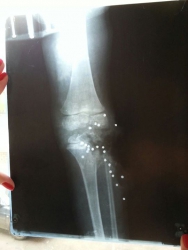

Напомним, по версии следствия, 22 июня Тимофей находился вместе с отцом, его другом и своим девятилетним старшим братом. У друга семьи с собой было огнестрельное оружие. Отец передал ствол старшему сыну, чему хозяин не воспрепятствовал, и мальчик, балуясь, выстрелил брату в ногу. Коленный сустав малыша оказался полностью разрушен. Теперь  ребенку предстоит очень длительное лечение - как рассказывала мать, до 20 лет ему предстоит пережить множество операций.

Сегодня корреспондент Saratovnews связался с отцом ребенка и сообщил более точную информацию. Одна из серьезнейших проблем - выстрелом были разрушены эпифизы длинных трубчатых костей ноги, в которых располагаются "точки роста". Каждые два года Тимофею предстоят операции для того, чтобы искусственно удлиннять кость, иначе нога просто не будет расти.